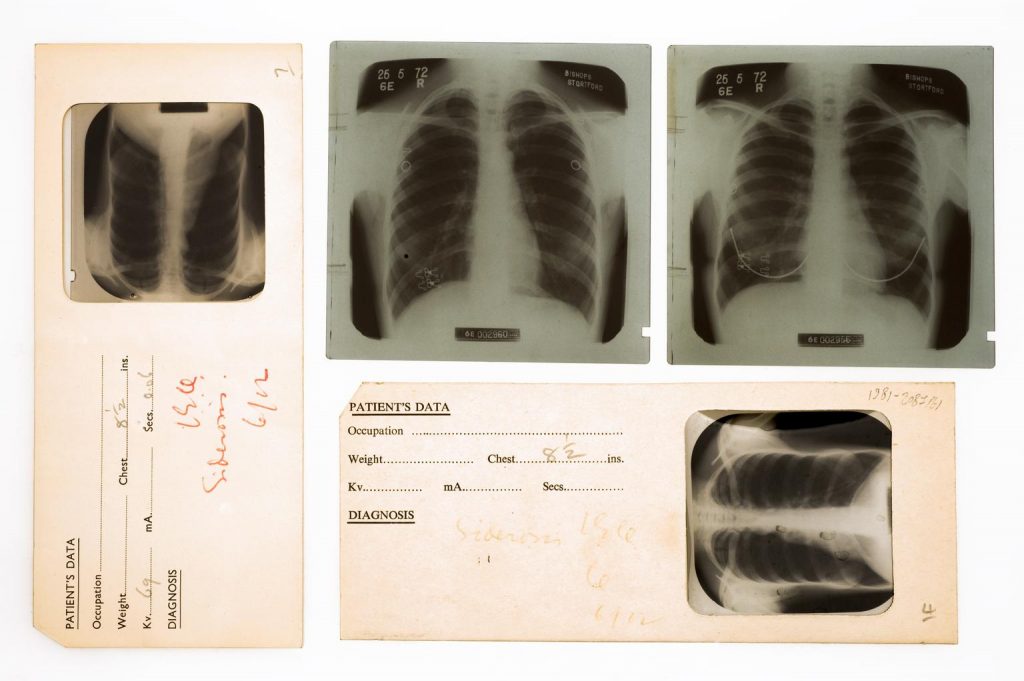

X-rays had at that time mostly been used to expose tumours and bone fractures, but Hart was curious about their potential to detect tuberculosis.

The disease usually begins to attack a patient’s lungs and can then then spread to the kidneys, spine, and brain. Hart realised that an early detection was crucial – both to isolate the victims and later, when antibiotics were discovered, to identify who was eligible for life-saving treatment.

By carrying out X-ray screenings of the chest, Hart was able to see signs of tuberculosis even before symptoms occurred.

This discovery was a game-changer for the Public Health sector and soon Hart became Tuberculosis Control Officer for the Idaho Tuberculosis Association. Between 1933 and 1945, he set up mobile TB screening units and together with his wife travelled across rural Idaho to make them accessible to all communities, providing discrete and safe spaces he called ‘chest clinics’.

Up until the 1970s, mass radiography campaigns were used all over the Global North, using buses, railroad cars, planes, and boats as mobile units to detect as many cases as possible before it could be passed on.